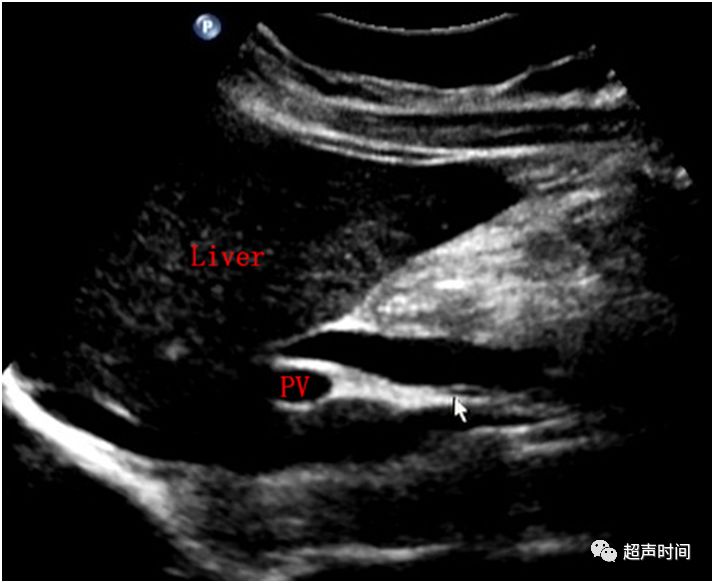

患者中年男性,以「间断性上腹部疼痛 7 年余,发作加重 1 周」就诊。超声检查发现胆囊结石、胆囊炎并肝门区胆总管扩张(图 1)。

图 1 A 示肝门处胆管轻度扩张;图 B 示胆囊囊壁增厚,粗糙,囊内见强回声,后伴声影,随体位改变而移动